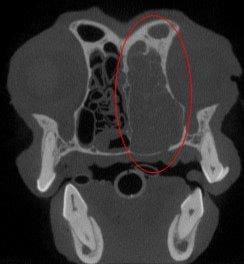

This dog came in for suspected periodontal disease but was found to have a large tumor in the right side of the nose. This tumor was not visible on dental radiographs and the dog did not have any obvious symptoms at the time. The circled area is the side with the tumor.